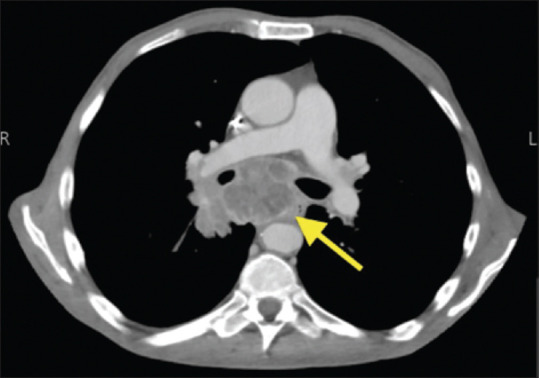

摘要:支气管镜检查是一种广泛用于诊断和治疗的技术。虽然它需要麻醉,但根据病人的健康状况、手术目的和所用支气管镜的类型,有许多选择。心力衰竭就是其中一种健康状况,它是导致死亡的主要原因,也是麻醉学的常见挑战。我们报告了一名 60 岁的男性患者,他已知患有射血分数为 15%的心力衰竭,植入了心脏除颤器,并同时患有缺血性心脏病、糖尿病和高血压,主诉吞咽困难。考虑到他无法使用传统方法,这名高度病态的患者在神经阻滞麻醉下成功接受了支气管镜活检。本报告旨在阐明这些具有挑战性的病例,并提醒麻醉医师如何处理心脏疾病患者的此类情况。

Abstract: Bronchoscopy is a widely used technique for diagnostic and therapeutic purposes. Though it requires anesthesia, many options are available, depending on the patient's health status, the purpose of the procedure, and the type of bronchoscope used. One such health status is heart failure, a leading cause of death, and a common challenge of anesthesiology. We report a 60-year-old male patient who is a known case of heart failure with an ejection fraction of 15%, and an implanted cardioverter defibrillator, along with concurrent ischemic heart disease, diabetes mellitus, and hypertension, who presented complaining of dysphagia. This highly morbid patient was able to successfully undergo a bronchoscopic biopsy with nerve block anesthesia considering his inadequacy for conventional methods. This report aims to shed light on these challenging cases and alert anesthesiologists on how to manage such situations in patients with cardiac morbidities.